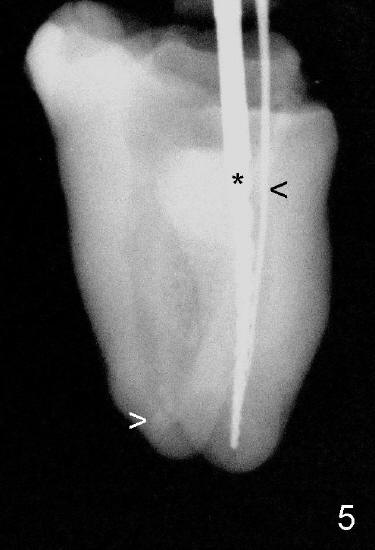

The most apical portion of the distal canal is found to be blocked (Fig.5 white >) when filling material is removed. The blockage is pre-existing, since it is present in Fig.4. The mesiobuccal canal (Fig.5 black <, #10 hand file) fuses with the mesiolingual canal (*, 30/.06 rotary file) before exit at apical foramen. Return to main text